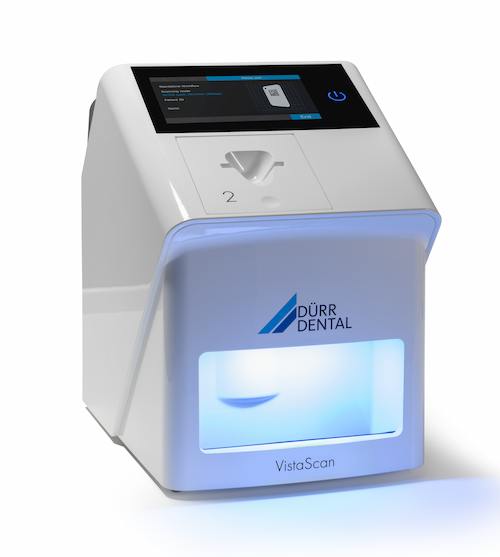

Read more/中文Our Technology

We have incorporated advanced dental technology into our practices to enhance the effectiveness of your treatment.

中文Digital Radiography

Reduced radiation exposure, improved image quality and faster results that can be easily stored, shared, and manipulated than traditional dental film.